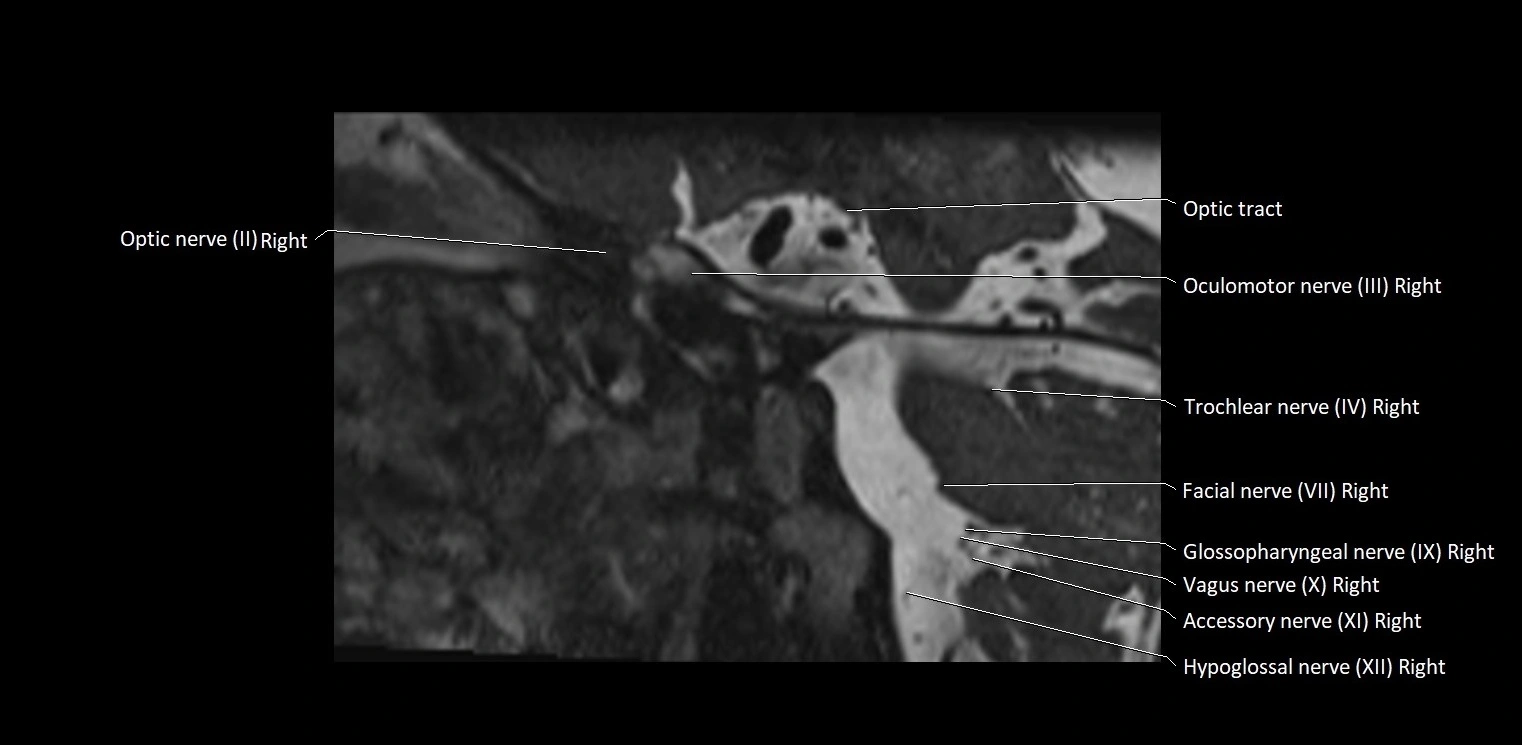

MRI Appearance

• The abducens nerve is a small, thin, linear structure

• Best visualized on high-resolution T2-weighted 3D MRI sequences (e.g., FIESTA or CISS)

• Seen as a hypointense (dark) line running from the brainstem at the pontomedullary junction, traversing the prepontine cistern, and entering Dorello’s canal under the petrosphenoidal ligament, then into the cavernous sinus, and finally the orbit

• May be challenging to visualize in standard MRI due to its small size

• Pathology may be inferred by absence, displacement, or enhancement of the nerve